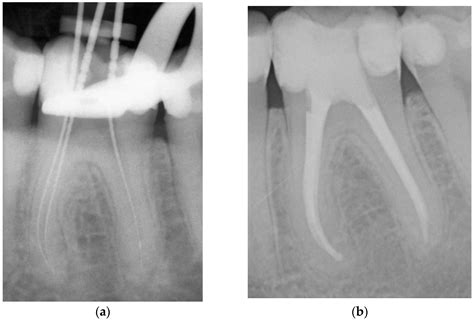

By specializing in the interior health of the tooth, these professionals utilize advanced technology, such as surgical microscopes and digital imaging, to perform intricate procedures. This high level of precision allows them to navigate the tiny, complex canals within the tooth roots to remove bacteria and restore function.

• Endodontic Retreatment: Sometimes, a previously treated tooth fails to heal or develops new problems months or years later. Retreatment involves reopening the tooth to address the complication.

The actual root canal or surgery involves isolating the tooth, cleaning the canals, and filling them with a biocompatible material called gutta-percha. After the procedure, the tooth is usually capped with a crown or filling to restore it to its full functionality. Most patients find that they can return to their normal daily activities almost immediately.

The field has evolved significantly over the past two decades. Today’s practitioners use ultrasonic instruments that can gently clean the inside of a tooth without the vibration associated with older dental tools. Furthermore, the use of operating microscopes allows the specialist to see tiny, hidden canals that might be missed by the naked eye. These technological leaps ensure that the treatment is not only faster but significantly more effective at preventing the recurrence of infection. By focusing on the microscopic details of the tooth's anatomy, endodontists are successfully saving millions of teeth annually that would have otherwise been extracted.